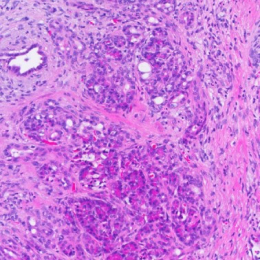

Step into the future of oncology with Lambda AF Solution’s Human Pancreatic Cancer Organoids. Crafted with cutting-edge 3D culture technology, these organoids bring the complex environment of pancreatic cancer right to your lab. Perfect for delving into tumor heterogeneity and enhancing drug testing—pioneering precision medicine starts here!

Pancreatic cancer organoid

H&E | ANXA1 | ANXA10 | ANXA13 | |

|---|---|---|---|---|

Cancer tissue | ![]() | ![]() | ![]() | ![]() |

Cancer organoid | ![]() | ![]() | ![]() | ![]() |

Unlock the essence of precision in cancer treatment with our PC organoids, mirroring the genetic markers of pancreatic cancer.